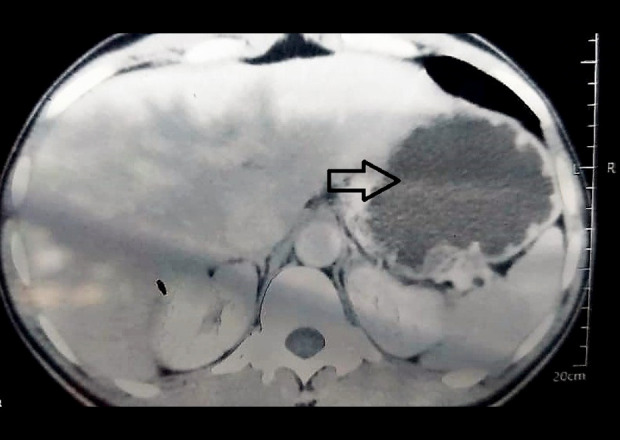

本报告描述了一名36岁男性,因特发性回盲肠肠套叠而出现严重腹痛和小肠梗阻的病例。肠套叠是指肠的一段延伸或折叠到它的远端。这是儿童人群中小肠梗阻的主要区别之一,但在成人中仍然非常罕见。成人肠套叠通常与消化道器质性肿物有关,尤其是肿瘤,它作为牵引点,将近端肠拖入远端肠段。在没有明显潜在肠道病理的成人患者中发现肠套叠是非常罕见的。病例报告:我们报告一例成年患者的回盲肠肠套叠,手术探查和病理检查均未发现潜在的肠道异常。患者,36岁男性,表现为剧烈腹痛,通过计算机断层扫描(CT)诊断为肠套叠。药物治疗失败后进行手术切除和肠吻合术。患者术后一个月出现腹泻和维生素缺乏性神经病变,诊断为短肠综合征,经适当治疗后痊愈。结论:肠套叠虽然在成人患者中很少见,但即使没有潜在的肠道疾病也可能发生。然而,彻底的手术探查和适当的病理分析对于排除其他肠道异常至关重要。临床医生应该意识到可能的并发症,如短肠综合征,如果采用手术方法和大量的肠道被切除。

BACKGROUND This report describes the case of a 36-year-old man presenting with severe abdominal pain and small-bowel obstruction due to idiopathic ileo-cecal intussusception. Intussusception refers to the telescoping or folding of a segment of bowel into the section distal to it. It is one of the main differentials of small-bowel obstruction in the pediatric population, but remains exceedingly rare in adults. Intussusception in adults is generally associated with organic masses of the digestive tract, especially tumors, which act as lead points that drag the proximal bowel into a more distal segment. It is extremely uncommon to find intussusception in an adult patient with no obvious underlying bowel pathology. CASE REPORT We report a case of ileo-cecal intussusception in an adult patient that yielded no underlying bowel anomaly on surgical exploration and pathology. The patient, a 36-year-old man, presented with severe abdominal pain and was diagnosed with intussusception through computed tomography (CT) scanning. Surgical resection and anastomoses of the bowel were subsequently performed when medical therapy failed. The patient experienced diarrhea and vitamin-deficient neuropathy a month after surgery, which was diagnosed as short bowel syndrome, and which resolved with appropriate medical care. CONCLUSIONS Intussusception, while rare in adult patients, is possible even without underlying bowel disease. However, a thorough surgical exploration and proper pathology analysis are essential to confidently exclude other gut anomalies. Clinicians should be aware of possible complications like short bowel syndrome if the surgical approach is used and a significant amount of intestine is resected.